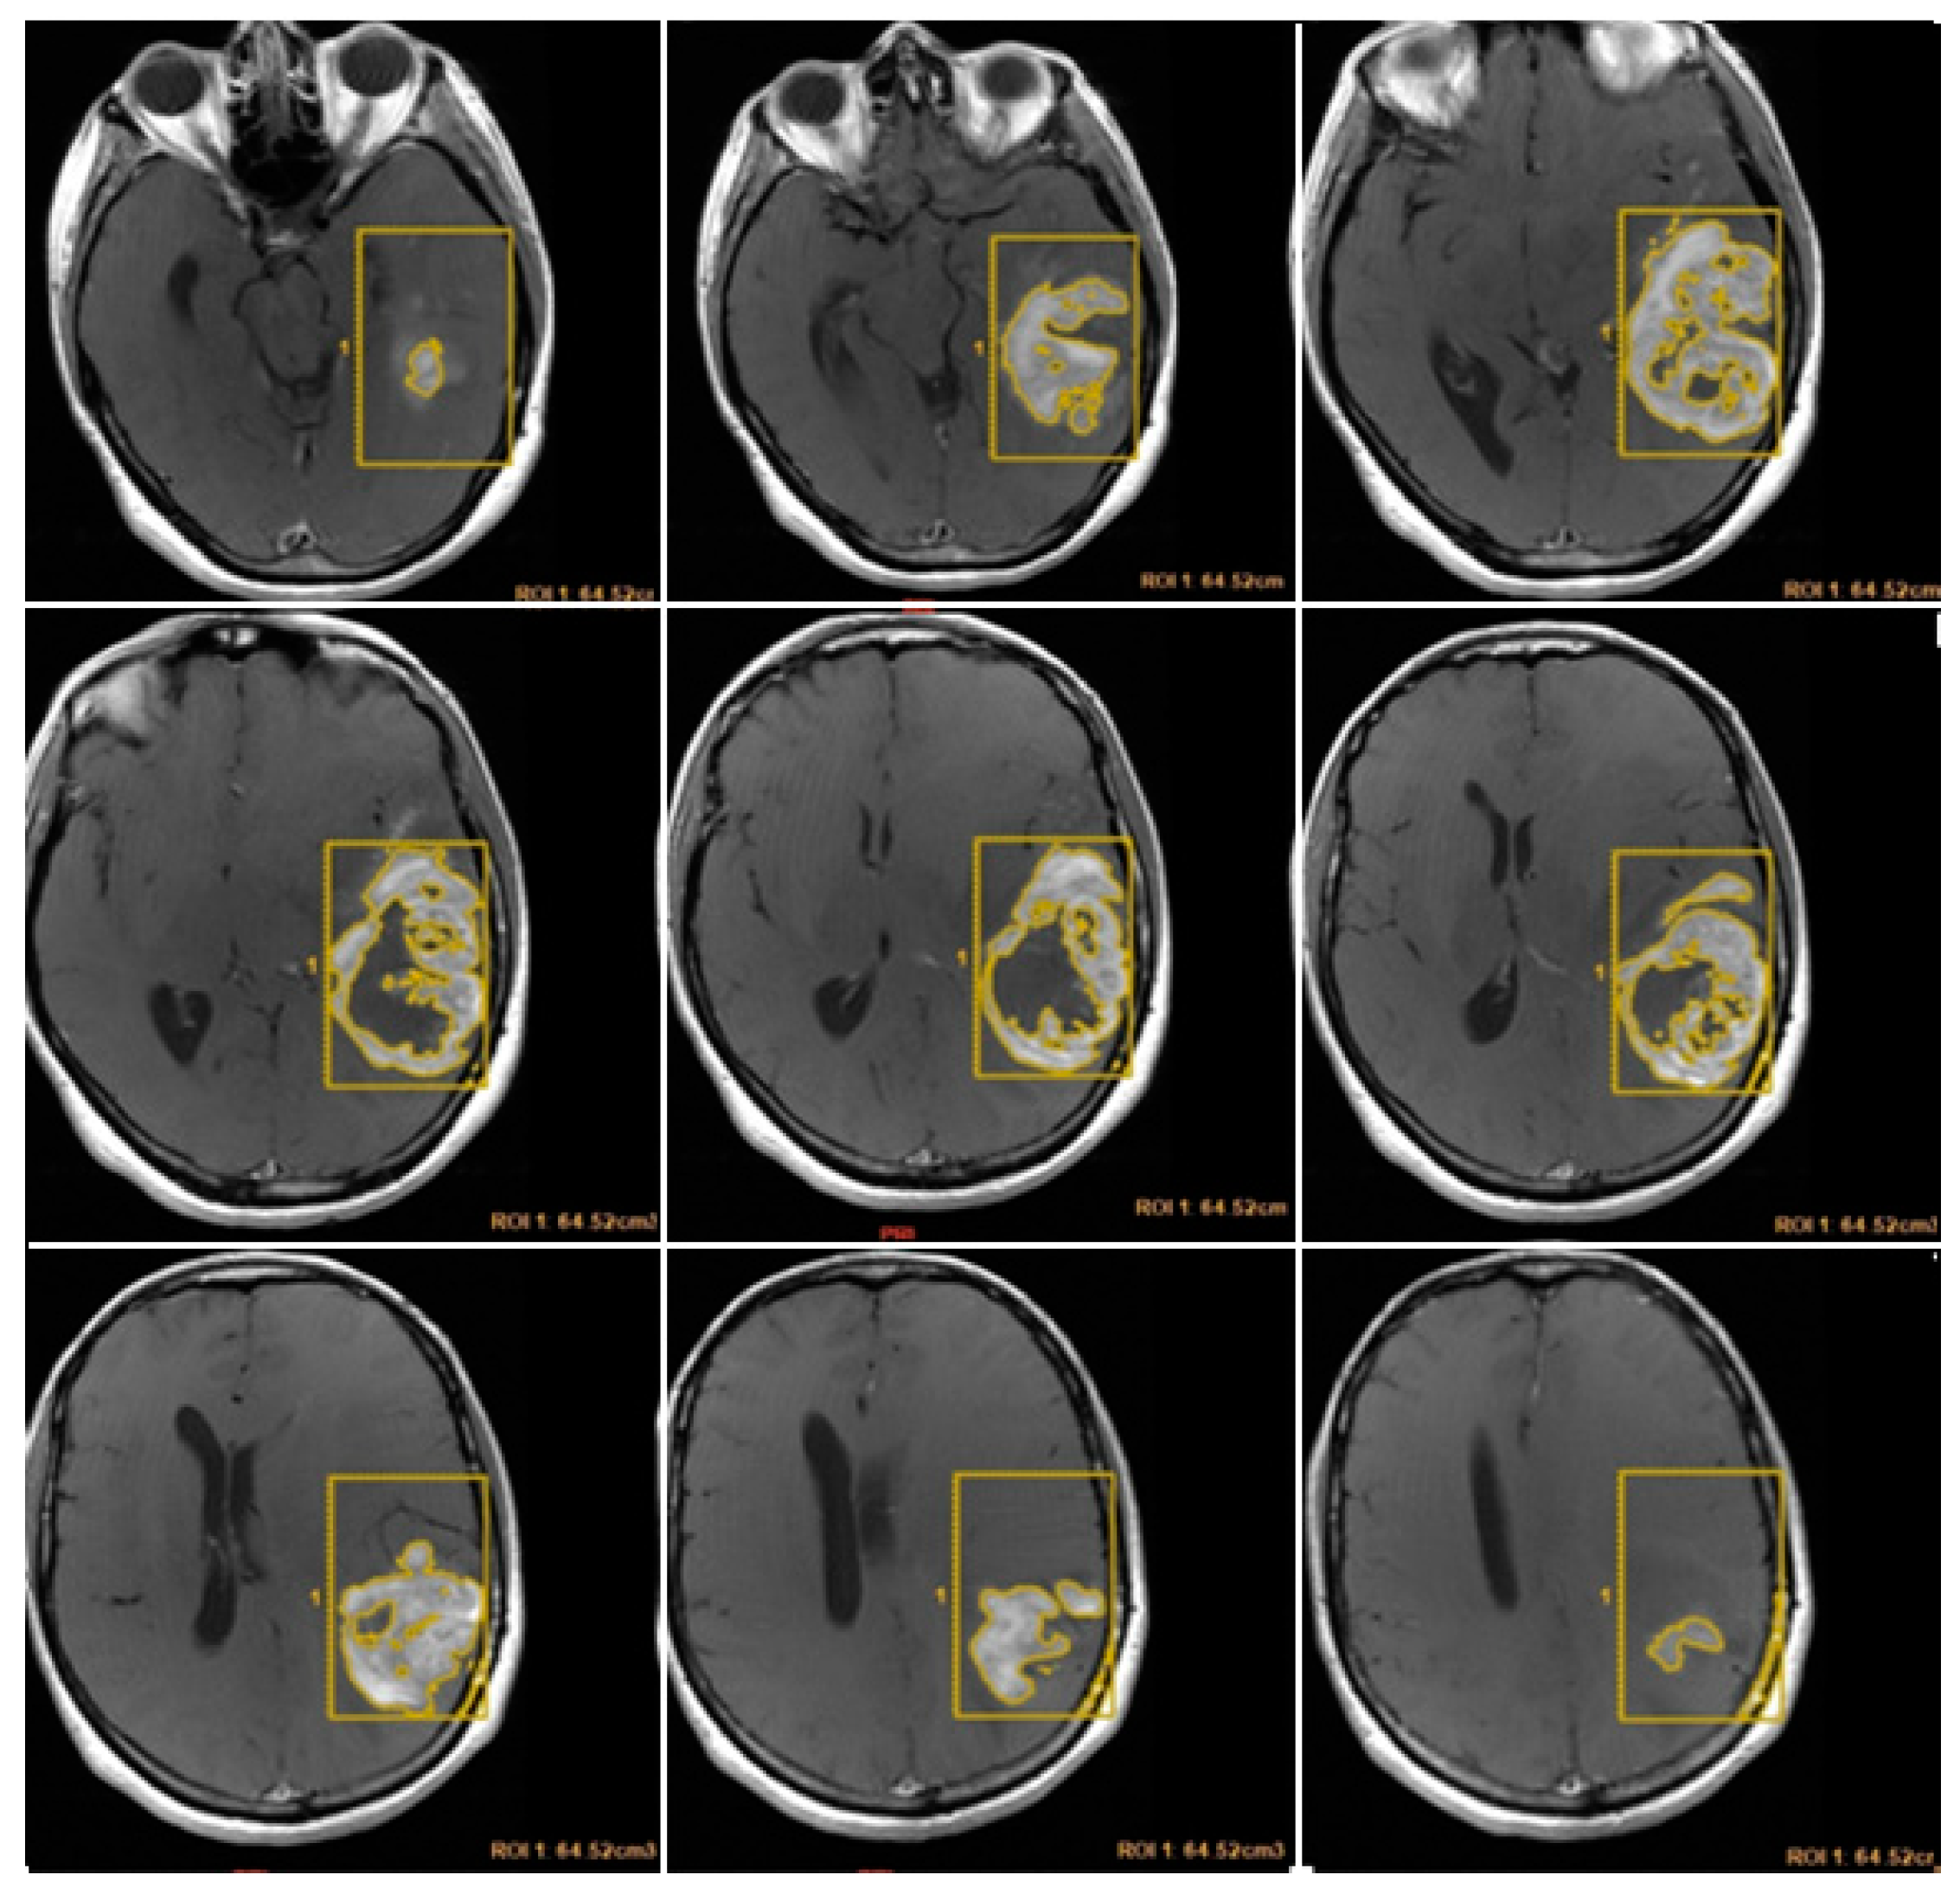

CE-RTV was assessed on 2D axial CE-T1w images (slice thickness: 5 mm.; slice spacing: 5,5-6 mm.), achieved with subtraction imaging technique to minimize errors due to the spontaneous hyperintensity of degradation products of hemoglobin or related to the presence of haemostatic/chemotherapeutic agents in the surgical area. As for CE-PTV, the analysis was performed both manually and semi-automatically [Figure 3 and Figure 4].

Figure 4. Contrast Enhancement Postoperative Tumor Volume (CE-RTV) semi-automatic evaluation.

Preprints 86216 g004